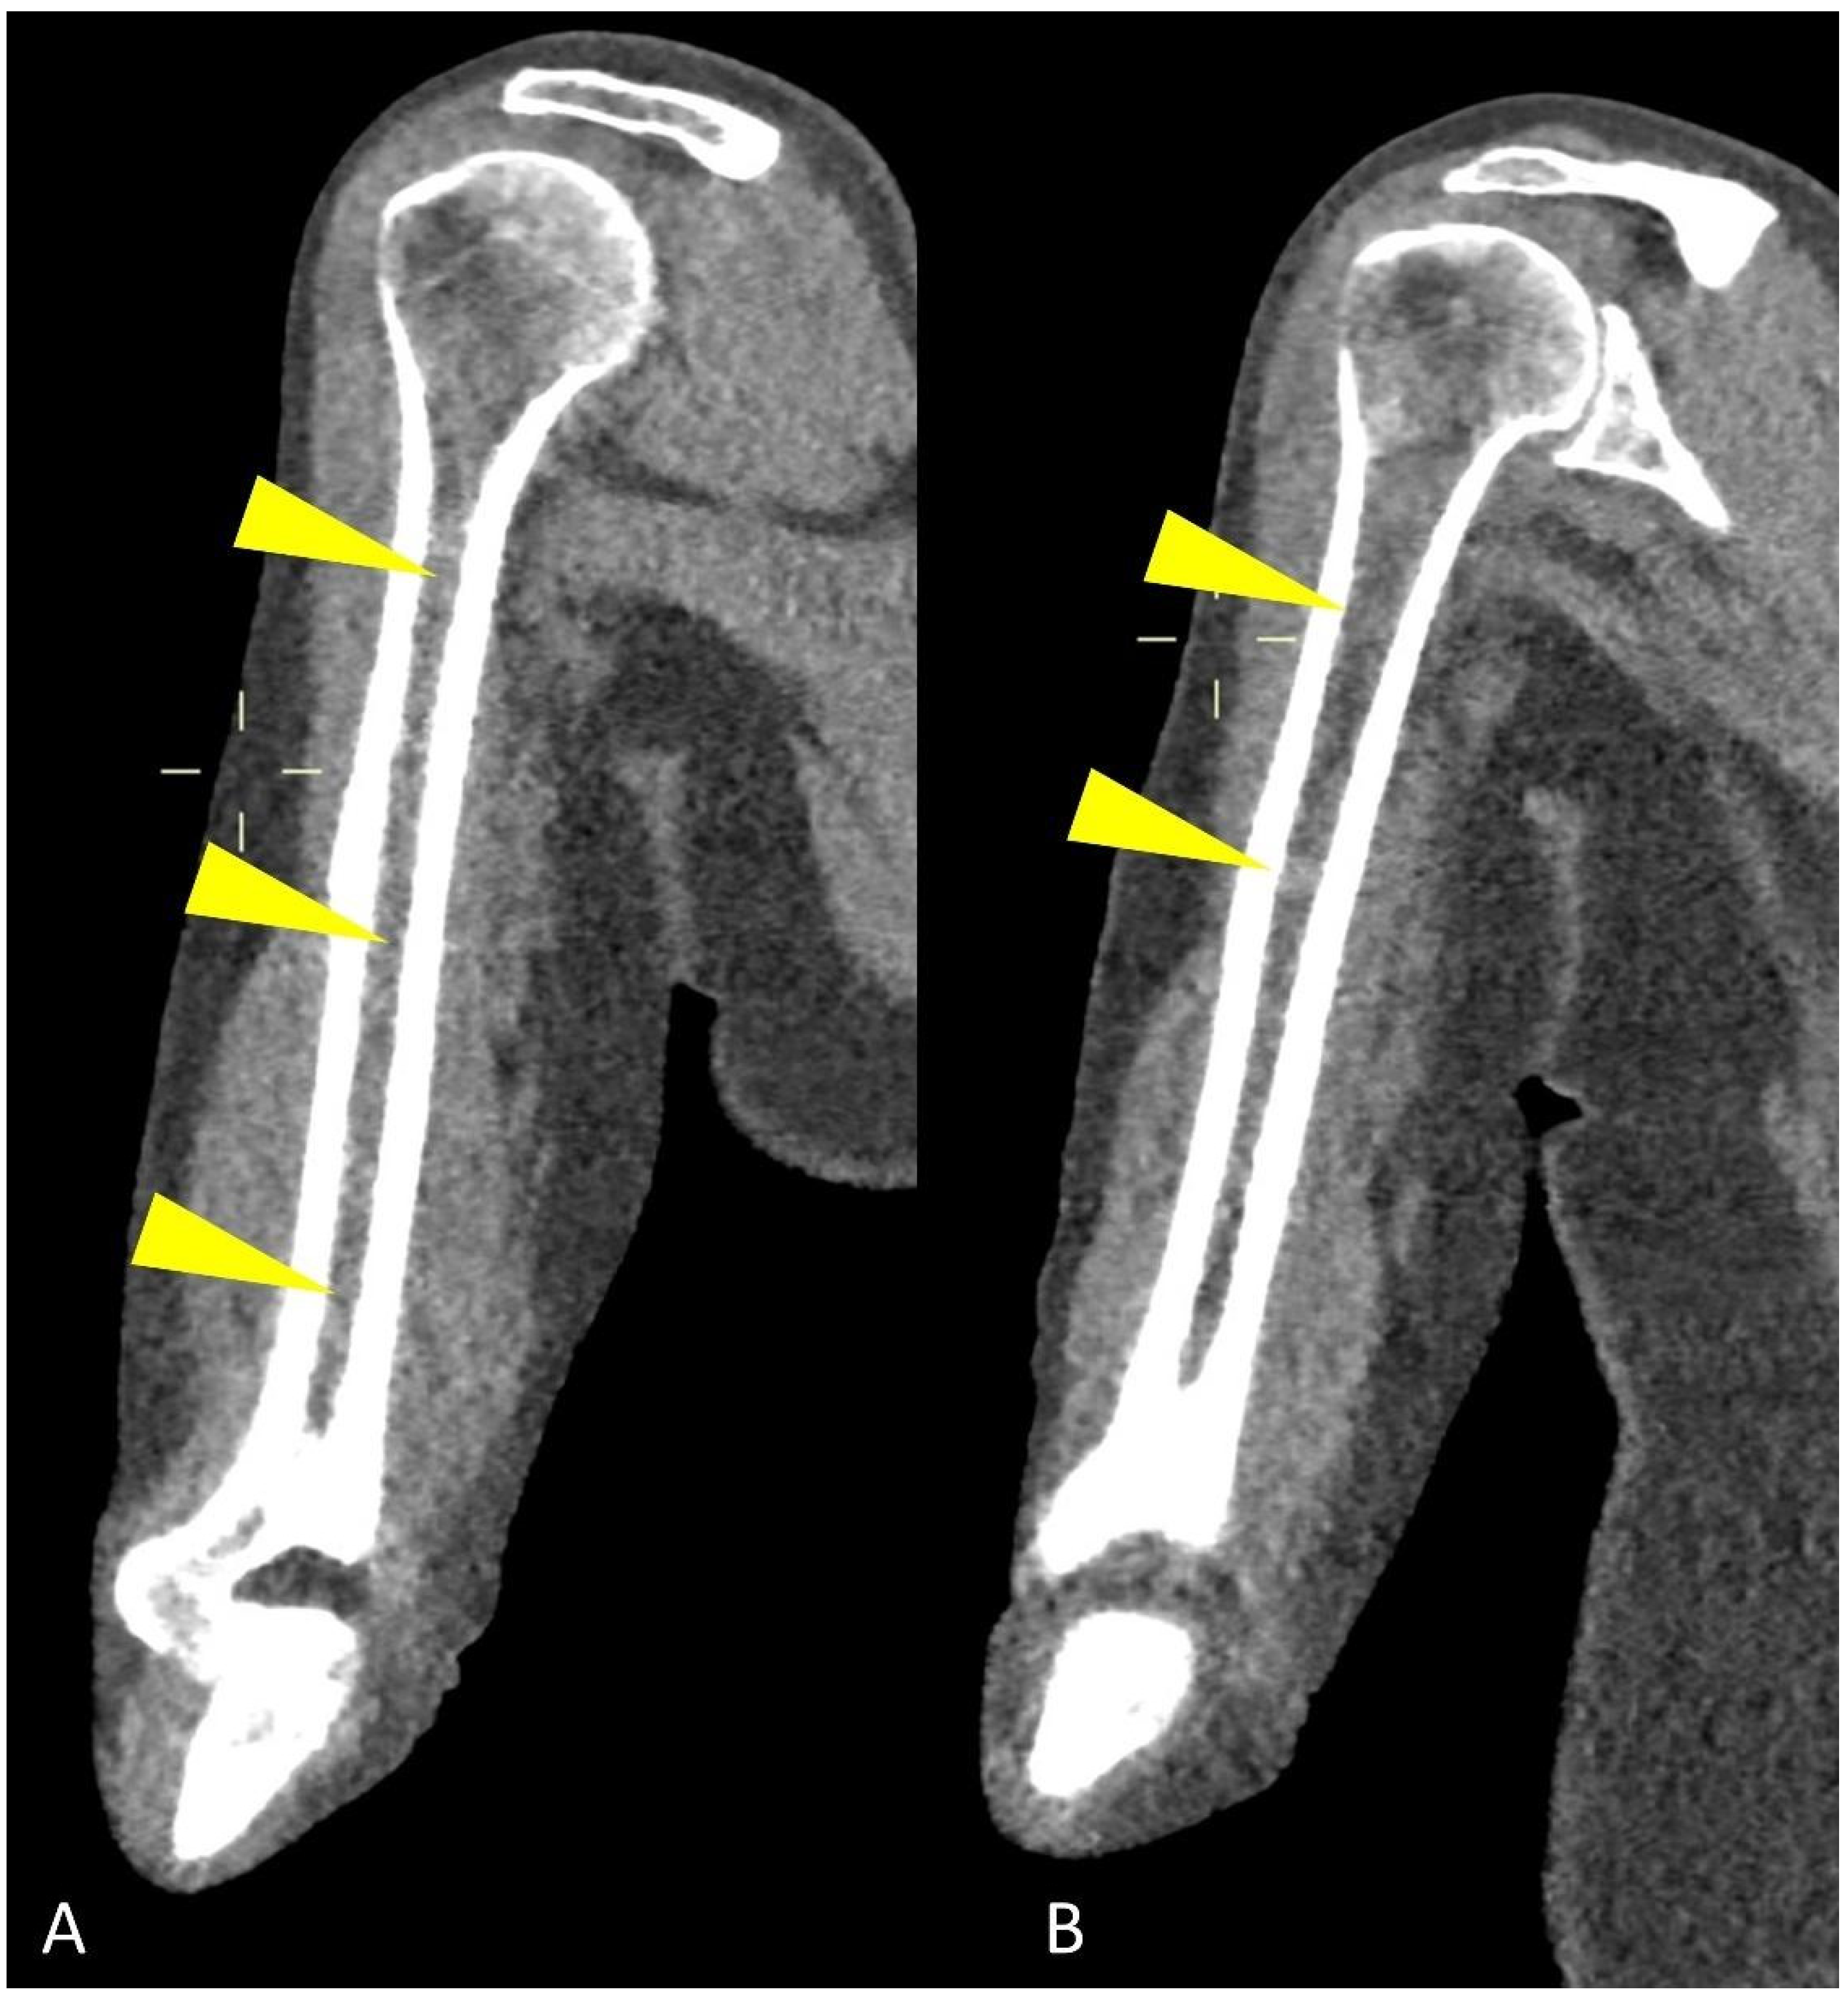

Study protocol usually requires at least a 64-slices scanner CT with the following acquisition parameters: 120 kV tube voltage and 30 mAs tube current, even though protocol variations using 140 kV tube voltage with 14 to 25 mAs current showed to be effective as well [16,17]. Increased radiation intensity up to 40 or 50 mAs is suggested for overweight patients and with known or expected reduced bone density [14]. Dual-Energy CT (DECT) protocols, exploiting the different attenuation of pathological and normal bone findings at different kV tube voltages, could be helpful in differential diagnosis [18]. Rebuilding algorithms help assess the quality of bone structure and para-medullary and extra-medullary soft tissues, as well as being the most powerful solution for evaluating focal and diffuse high-density myeloma deposits in the long bone marrow cavity (Figure 2).

Figure 2.

Coronal CT image showing (yellow arrowheads) humeral abnormal medullary lesions with high CT density in a patient with MM with (A) diffuse and (B) focal pattern.

Axial images using a “bone” reconstruction algorithm must be systematically performed, usually in a cranio-caudal fashion, starting from the skull to the cervical, thoracic, and lumbar spine, pelvic bones, and lower limbs, whereas ribs, sternum, scapulae, clavicles, and upper limbs are evaluated afterward (Figure 1B). Once completed, it is advisable to analyze the sagittal multiplanar reconstruction (MPR) images of the spine to identify vertebral fractures and to assess the risk of neural compression (Figure 1C). MPR images are also useful to differentiate benign osteoporotic vertebral fractures from malignant ones (although MRI remains the gold standard for differential diagnosis of vertebral collapse): predictive CT findings of benign vertebral fractures are the presence of fracture lines within vertebral body, retropulsion of a bone fragment from posterior wall into the spine canal, evidence of paraspinal soft tissue widening, and intravertebral “vacuum sign” defined as the presence of an air cleft in the vertebral body. Features associated with malignant vertebral fracture are the presence of extended destruction of the vertebral body (cortex and cancellous bone) and pedicles, as well as a focal soft tissue mass in the paravertebral or epidural space [15]. Focal and/or diffuse intra-medullary infiltration of femur and humerus can be found by analyzing axial and MPR images (Figure 2 and Figure 4) [22].

Infiltration of the humeral and femoral bony canals can be classified as focal or diffuse according to the pattern of the dense area (Figure 2): the diffuse pattern is defined as the homogenous opacity of the bony canal, whereas the focal pattern was defined as the presence of one or more focal high-density areas; evaluating these peripheral medullary deposits on WBLD-CT is critical since they can be linked to high tumor burden, advanced disease stage, and poor prognosis in patients with symptomatic myeloma [18].